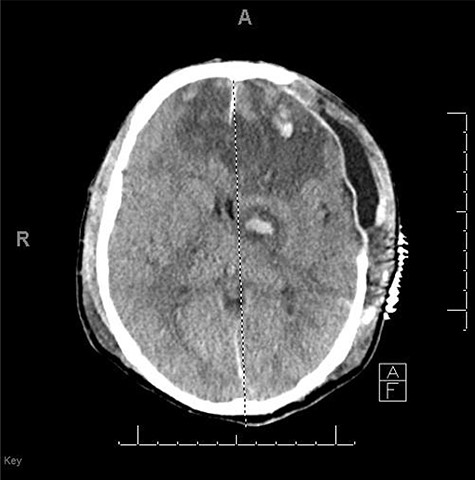

He was paralyzed, intubated and taken emergently to the OR due to nonresponsive hypovolemic shock. A right frontal ICP monitor was placed in the operating room while he was undergoing an emergency thoracotomy. Intraoperative ICP was in the 40s, and thus the patient was taken directly from the operating room to CT scan which showed enlargement of bilateral contusions, left greater than right, for which he was taken emergently to the operating room for a left hemicraniectomy (Figs 2 and 3).

CT head post thoracotomy with expansion of contusion with shift.